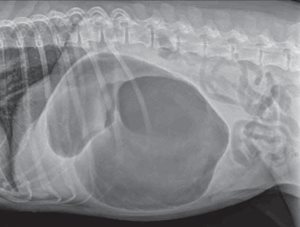

Prise en charge préopératoire (Photos 2 et 3)

Photo 2

L’hémorragie et les coagulopathies constituent les principaux risques peropératoires en cas de splénectomie.

Il est donc recommandé de réaliser un bilan biologique (numération-formule sanguine, biochimie, ionogramme, exploration de l’hémostase) avant d’envisager une anesthésie.

Une transfusion sanguine est parfois nécessaire.